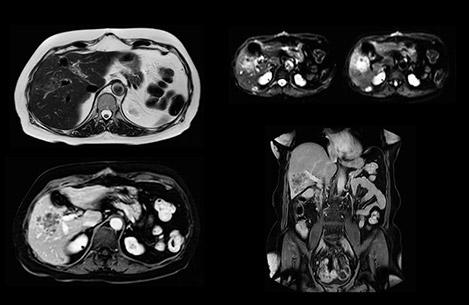

In this example the image quality of the MultiVane XD images is evidently better than in the images without MultiVane XD. Ingenia 1.5T with dS Torso coil solution.